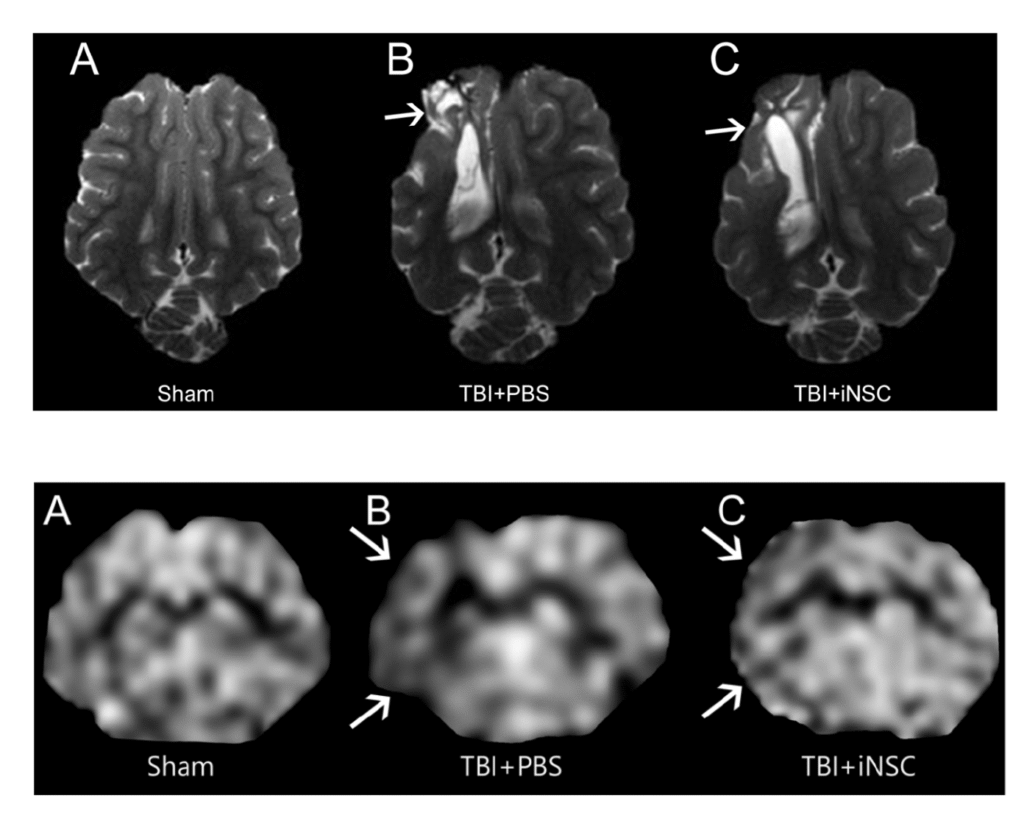

Top: Transplantation of stem cells decreased tissue atrophy and lesion volume in a study using piglet brains effected by TBI. Bottom: Transplantation of stem cells preserved cerebral blood flow in a study using piglet brains effected by TBI.

Scans courtesy of: Schantz, S. L., Sneed, S. E., Fagan, M. M., Golan, M. E., Cheek, S. R., Kinder, H. A., Duberstein, K. J., Kaiser, E. E., & West, F. D. (2024). Human-Induced Pluripotent Stem Cell-Derived Neural Stem Cell Therapy Limits Tissue Damage and Promotes Tissue Regeneration and Functional Recovery in a Pediatric Piglet Traumatic-Brain-Injury Model. Biomedicines, 12(8), 1663. https://doi.org/10.3390/biomedicines12081663